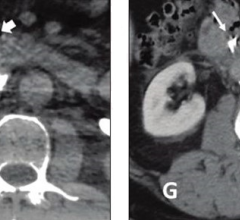

January 30, 2023 — Photon-counting detector CT reduces the amount of contrast needed for CT angiography (CTA) while ...